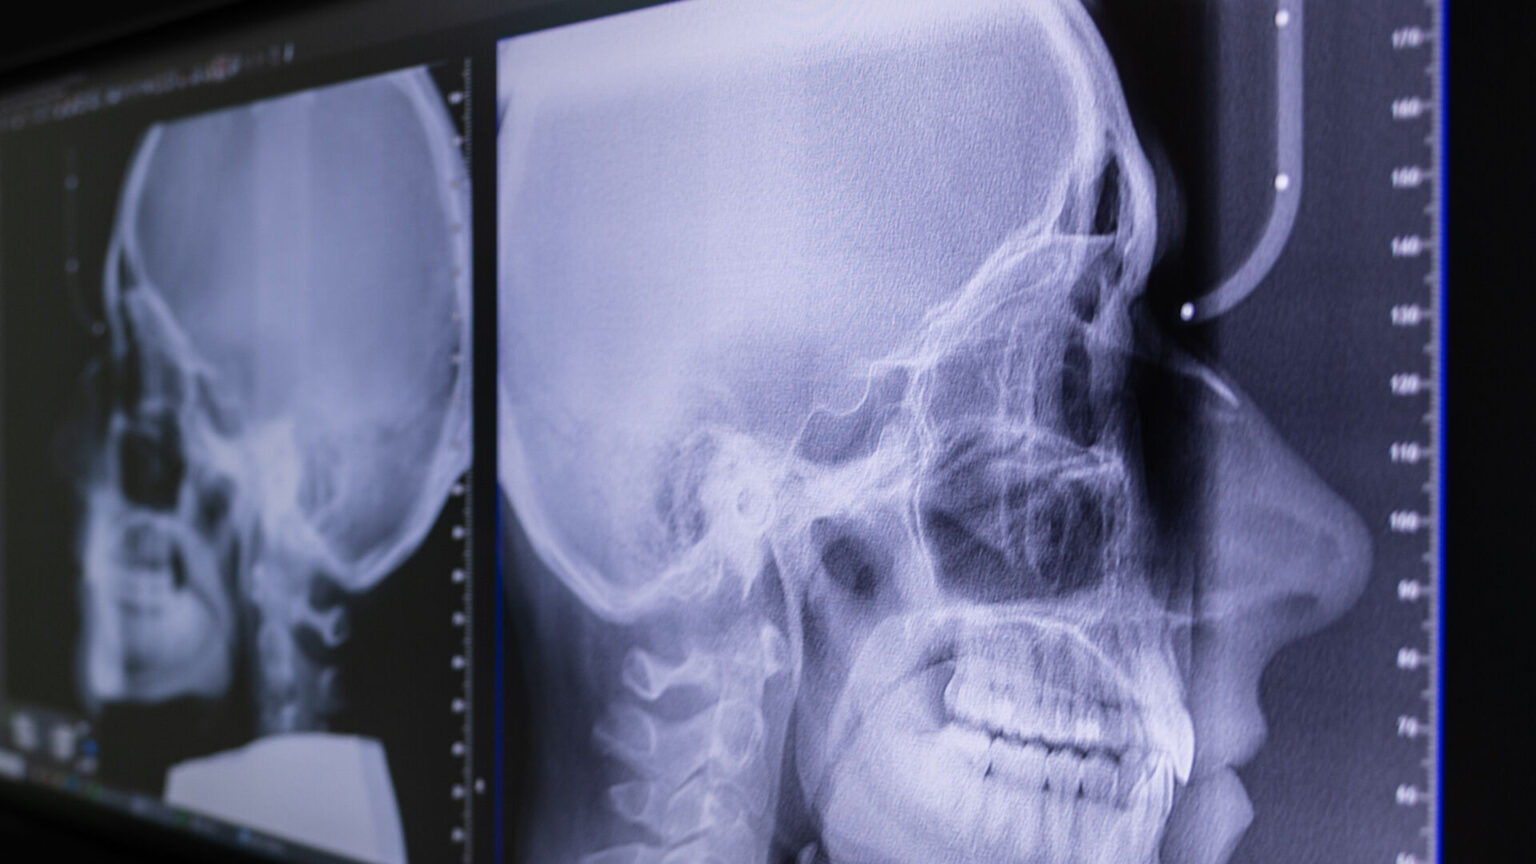

Známý také jako kefalometrický snímek nebo boční dálkový snímek hlavy. Jde o speciální typ rentgenového vyšetření, které se primárně využívá v ortodoncii a maxilofaciální chirurgii.

Hlavním účelem Tele rentgenu je získat přesný, standardizovaný snímek celé lebky z boku (profilový snímek). Tento snímek zobrazuje nejen zuby a čelisti, ale také okolní kostní struktury, měkké tkáně obličeje a lebeční bázi.